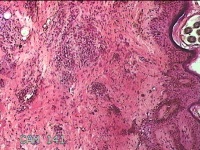

面部新生物

性别

女

年龄

47岁

临床诊断

纤维瘤

一般病史

面部新生物一月余。

标本名称

面部赘生物

大体所见

灰白粉红色肿物0.8x0.7x0.3cm一个,表面糜烂。

看似皮内痣,片子制片质量比以前有所提高,但仍需努力。楼主采图也要提高,重点对病变采图。

良性病变。